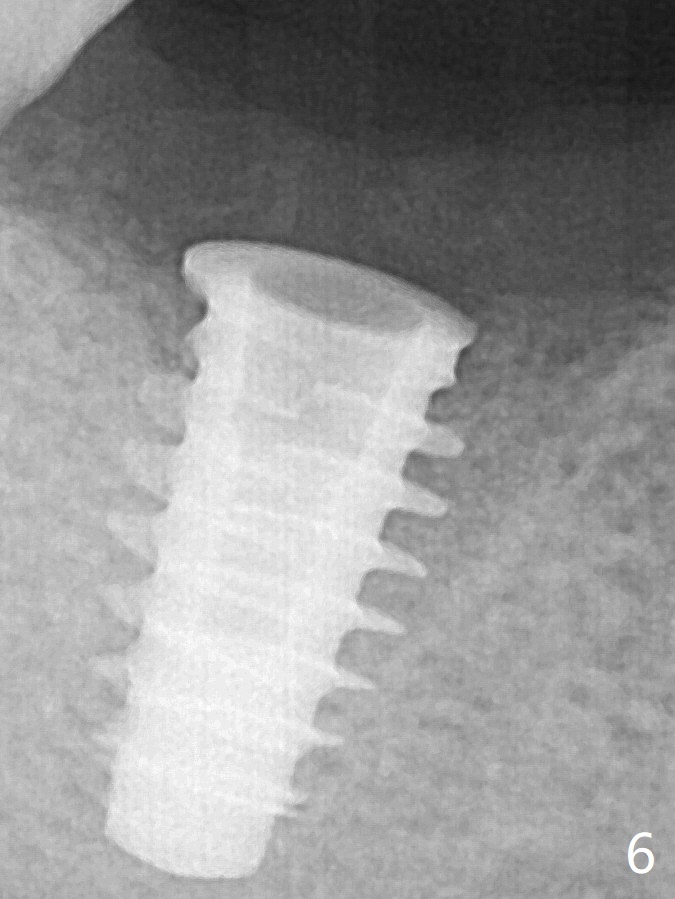

To reduce socket gap (*), a 6 mm IBS implant is inserted with >50 Ncm (Fig.5).  What is unexpected is heavy reduction in the height of a 6.5x4(3) mm abutment (A) because of the short crown height of the lower posterior teeth (Fig.1) and supraeruption of the tooth #3.  The immediate provisional is unstable postop.  The remade one dislodges soon, so does the abutment (Fig.6, 3 months postop).  It appears that bone pattern in the distal socket changes.